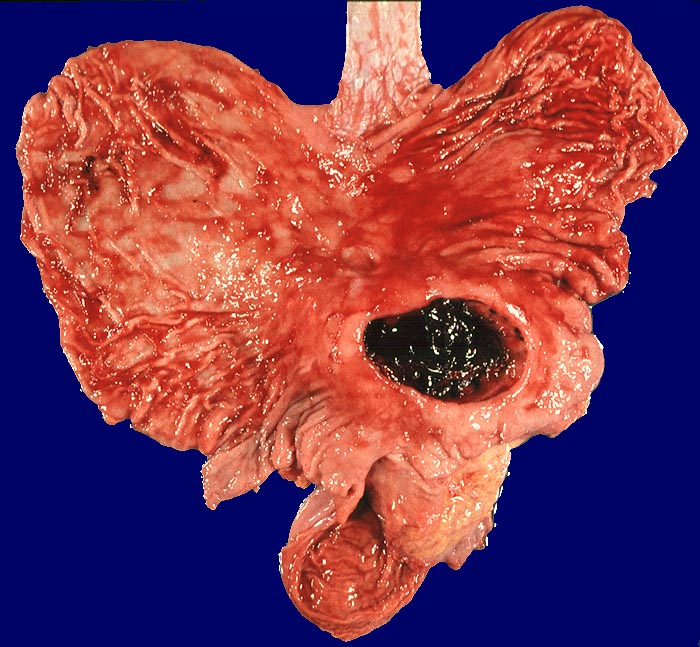

Das akute Ulkus ist rund, oval oder seltener polyzyklisch begrenzt und liegt meist im Schleimhautniveau. Das chronische Ulkus ist häufig kreisrund und im Längsschnitt trichter- oder treppenförmig. Die Schleimhautränder können lippenförmig über den Ulkusgrund hinausragen. Palpatorisch ist das chronische Ulkus aufgrund der narbigen Fibrose induriert. Die Schleimhautfalten laufen sternförmig auf das Ulkuszentrum zu. Das chronische Ulkus tritt zu 10%, das akute zu 25% multipel auf. Mikroskopisch zeigt das chronische Ulkus eine typische Schichtung (s. Bilder). Die Gefässe im Ulkusgrund zeigen eine starke Intimaproliferation mit teilweiser oder vollständiger Obliteration der Gefässlichtung. Morphologische Veränderungen in der übrigen Magenschleimhaut geben einen Hinweis auf die Ätiologie des Ulkus (Typ B oder C Gastritis).

Makroskopie

Befund

Pathologischer Befund